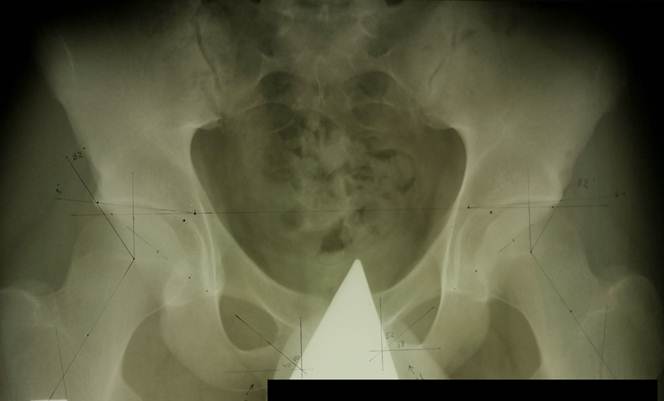

Снимок

описываемого больного, расчерчивание вручную. Обратите внимане на очевидно мелкие суставные впадины и сужение суставной

щели слева. Двухстороннее уменьшение

угла Виберга: 32° при норме не менее 39. Ацетабулярный индекс с обеих сторон в норме (

он несет значимую информацию о вертлужной впадине только в первые три года жизни). Угол Шарпа ( ≈40°) в норме.